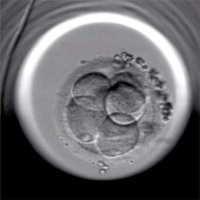

Fecundación in vitro, embrión, óvulo, FIV

GETTY IMAGES/ISTOCKPHOTO / LARS NEUMANN

La mejora de las técnicas de cultivo celular ha permitido alargar el tiempo durante el cual los embriones resultantes de la fecundación 'in vitro' se pueden mantener fuera del organismo materno sin comprometer su vitalidad.

Durante el cultivo prolongado se acentúa la diferencia entre la apariencia de embriones de buena calidad y los de una calidad inferior. Esto permite la evaluación más precisa de la condición de cada embrión y la selección de los mejores para ser transferidos en el útero.